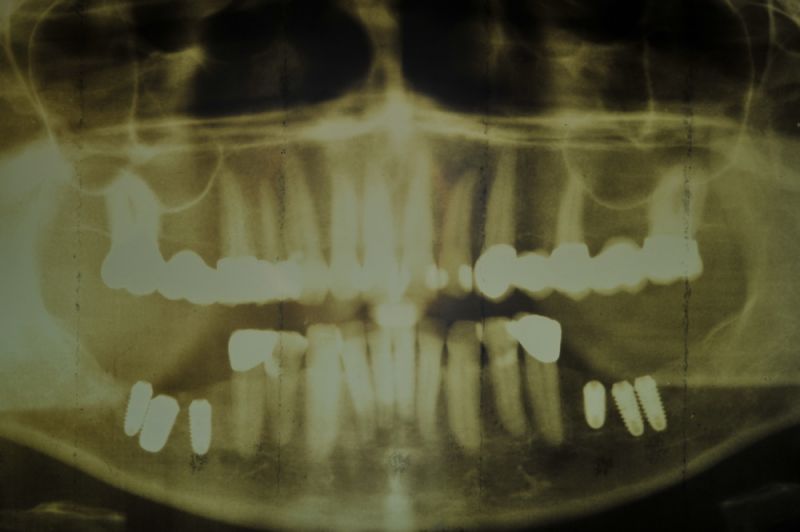

1. Notwendigkeit einer implantatgestützten Kronenversorgung mit der Vorgeschichte, dass die Patientin eine Vielzahl von Behandlern aufgesucht hatte, die eine Implantation im Unterkiefer als nicht durchführbar einschätzten.

2. Extrem schlechte knöcherne Verhältnisse im Unterkieferseitenzahnbereich, die sich intraoperativ noch einmal als ungünstiger darstellten, als bereits in den Voruntersuchungen erkennbar.

3. Sehr dünne Implantate, die von ursprünglich zwei je Kieferhälfte auf letztendlich drei je Kieferhälfte umgeplant werden mussten.